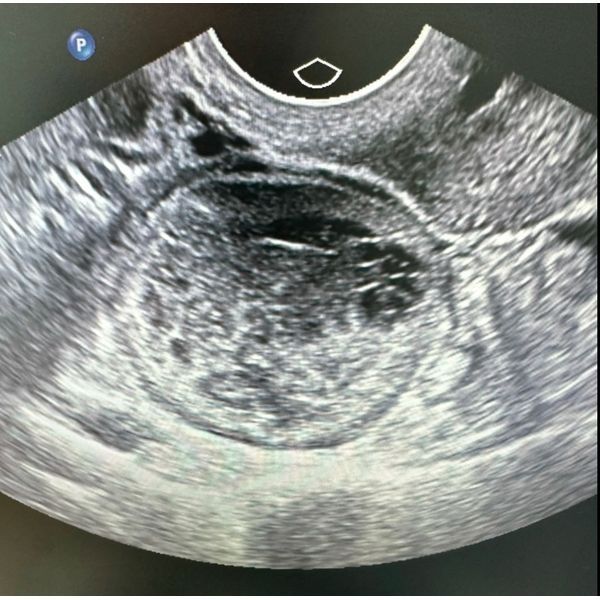

Склероз кисты